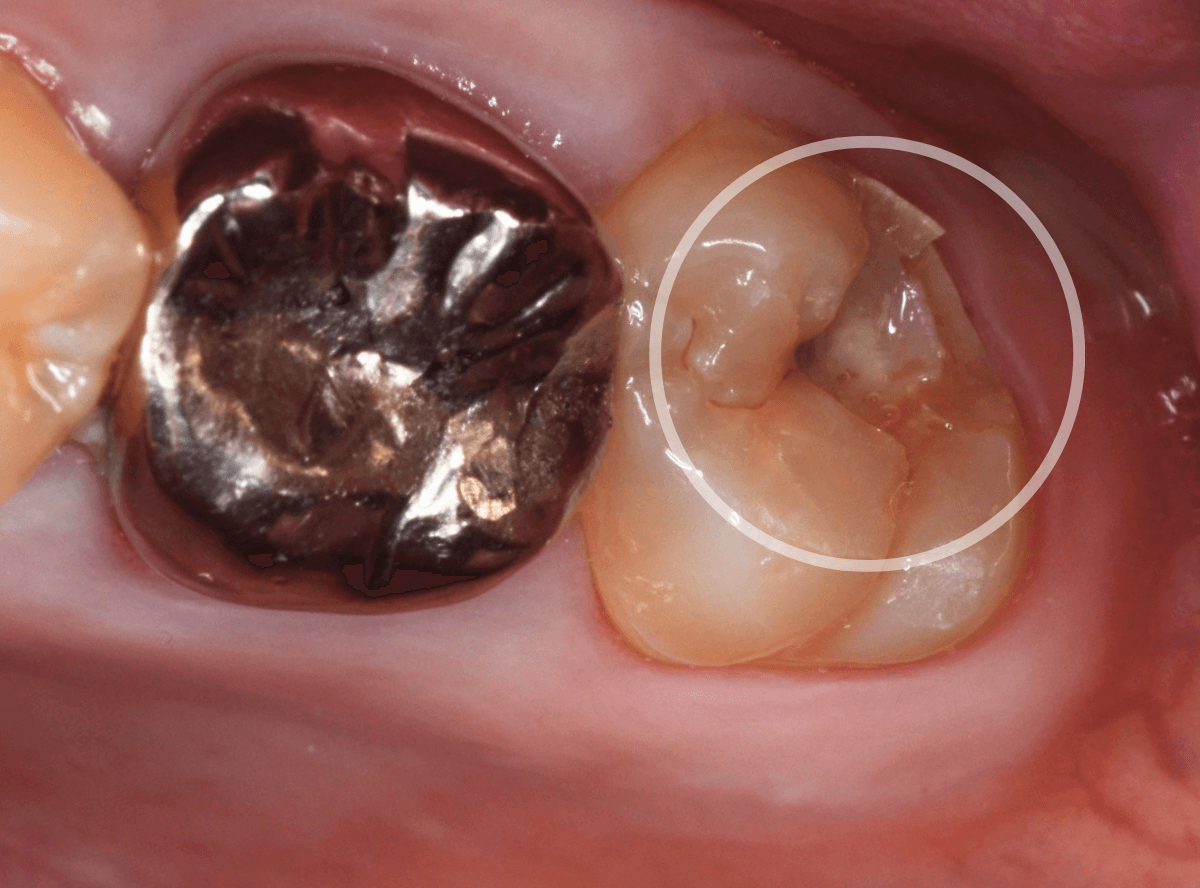

今回は、上のおやしらずが原因で虫歯になってしまった方のケースです。

〇部のおやしらずを虫歯で抜歯しました。

抜歯してしばらく経ったところです。

特に問題なさそうに見えますが、「おやしらずを抜歯してから、歯がしみるようになった」との訴えです。

これは、おやしらずを抜歯した後によくある症状です。

レントゲン写真で確認します。

青い線が歯の神経、赤い線が虫歯です。

おやしらずがあった際にはわかりづらかったですが、歯の後ろ側のおやしらずが重なっていたところが虫歯になっているのがわかります。

おやしらずが原因で、このように手前の歯が虫歯になってしまう事が多いために、抜歯を勧められる事が多いのです。

そして、虫歯の部分におやしらずが被さっていたために、しみる症状などを感じなかったのです。